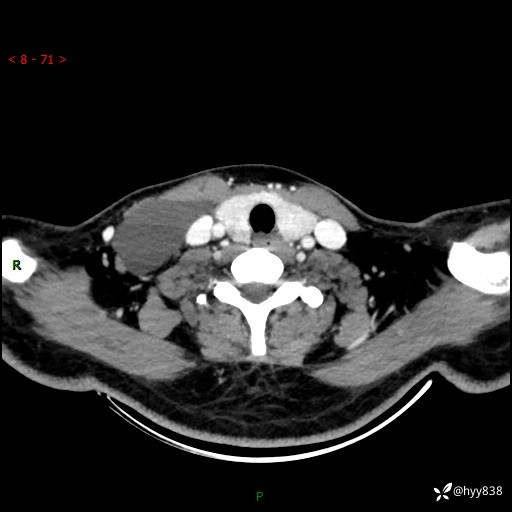

辅助检查:CT

颈部CT平扫

增强动脉期+静脉期